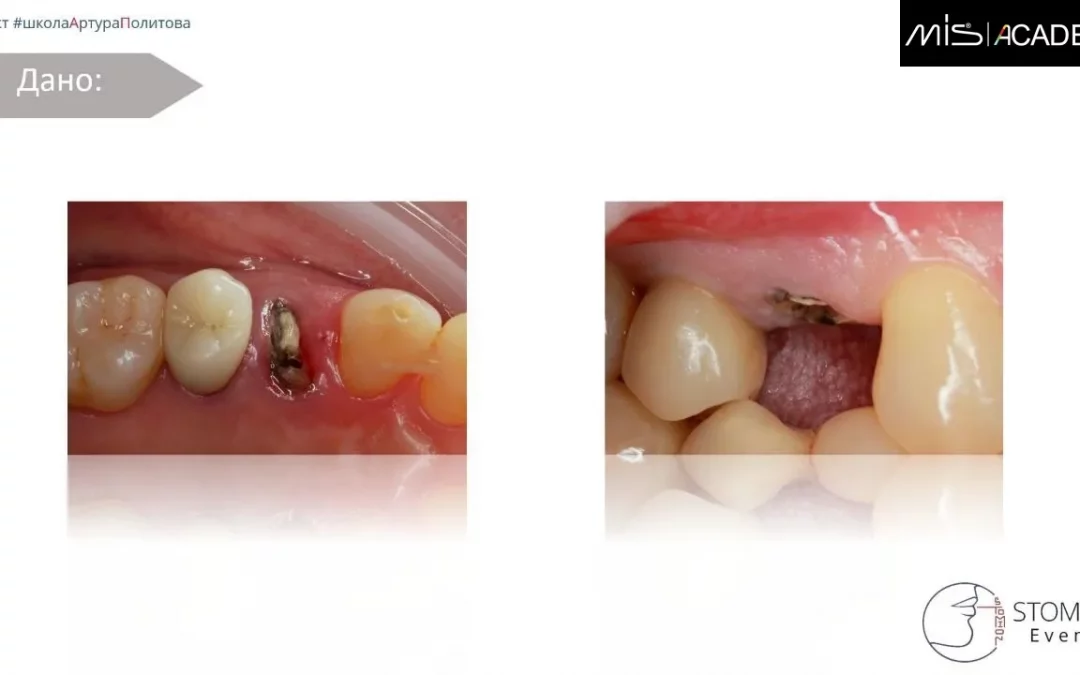

Артур Политов | Клинический кейс AP-77

Одномоментная имплантация Удаление 1.4. Формирование гомогенного кровяного сгустка. Одномоментная имплантация в нёбный корень MIS C1 3,75x11,5. СТТ с бугра вестибулярно. Коннект абатмент, индивидуальный ФДМ...